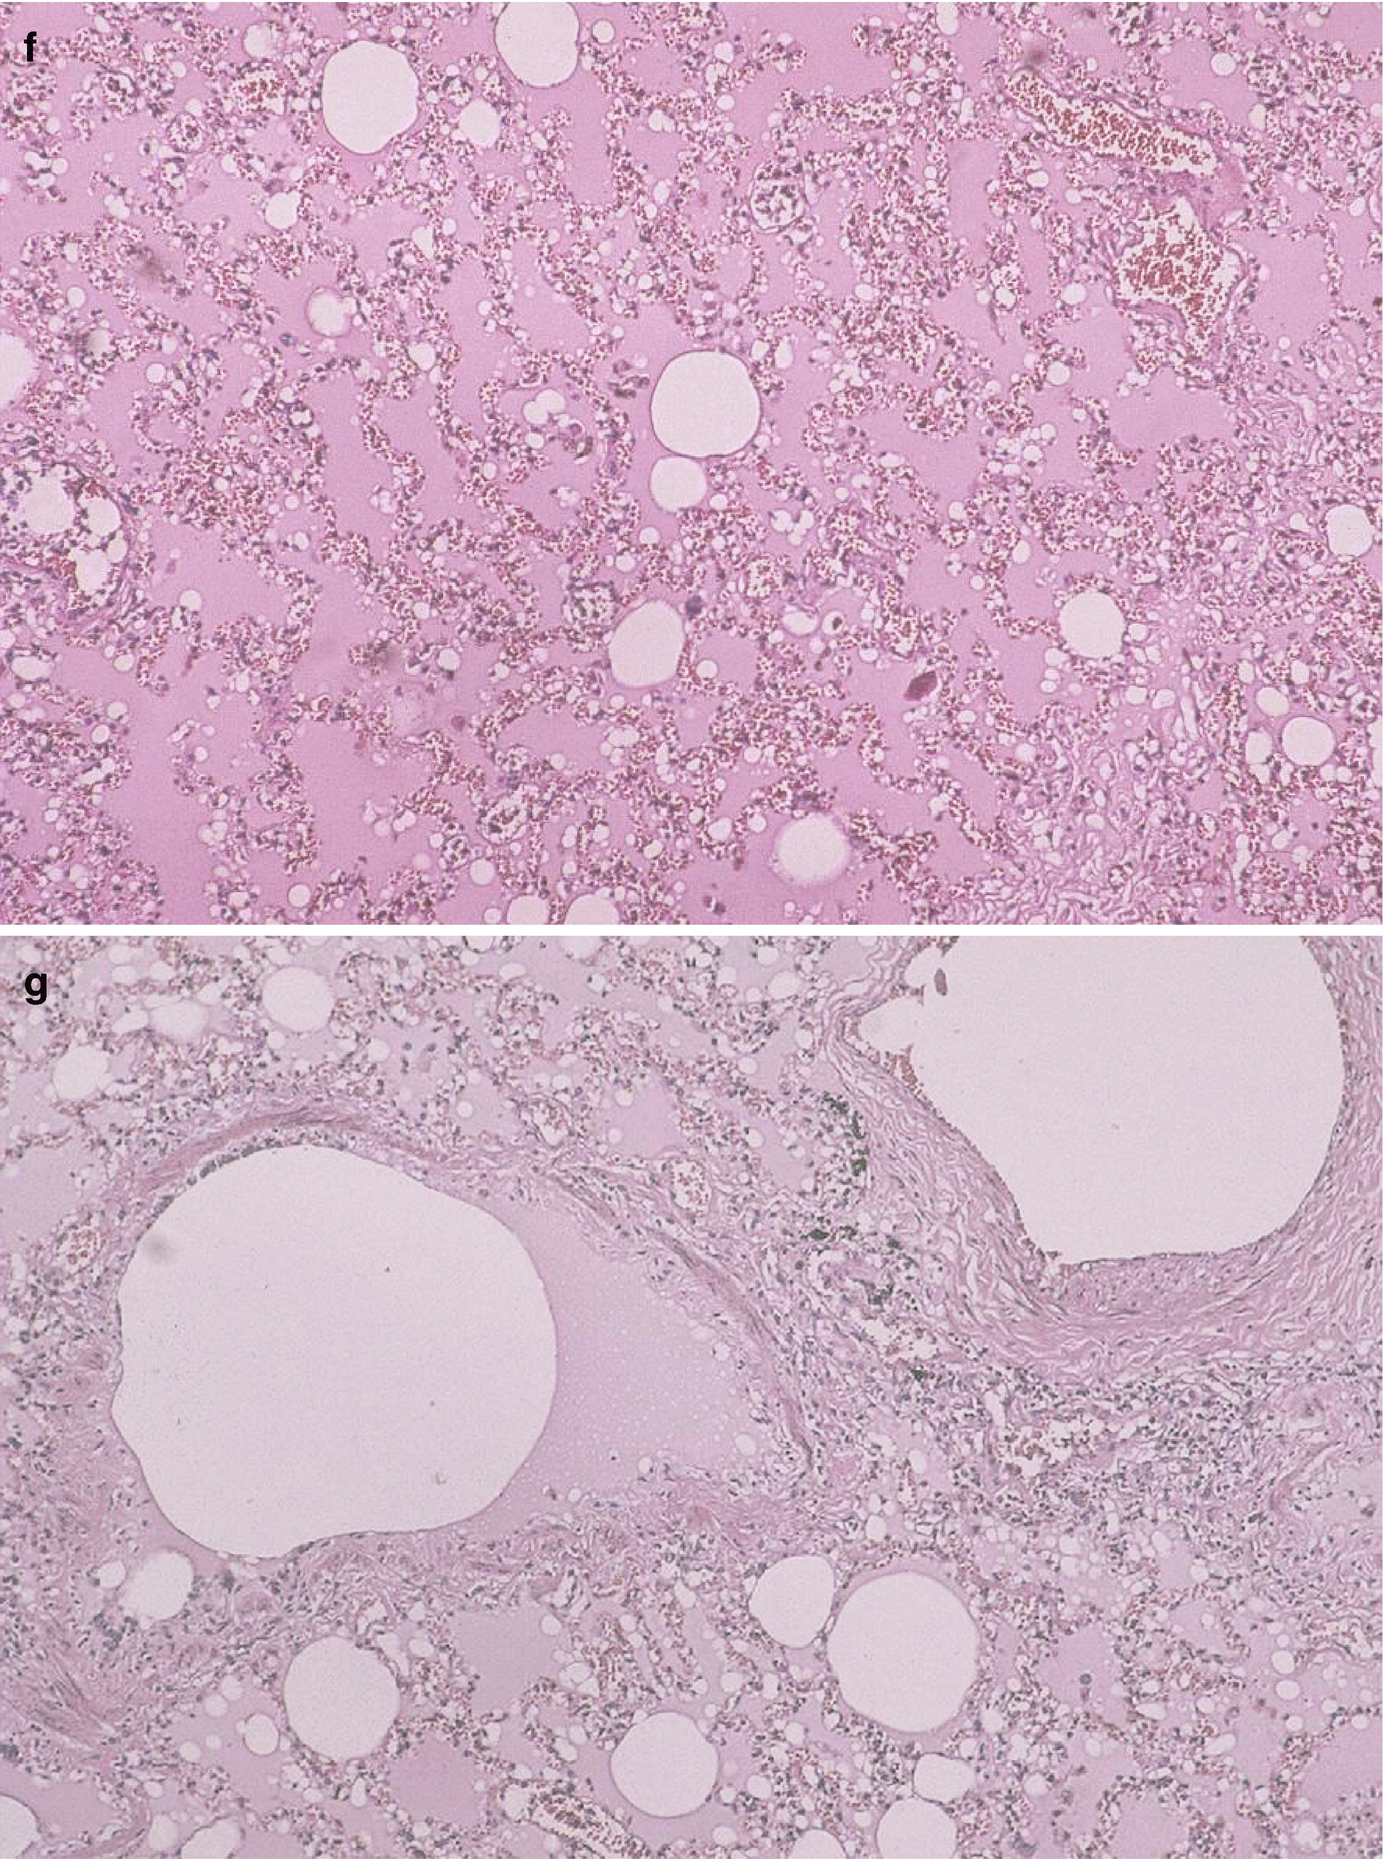

Patient deceased due to pulmonary silicone embolism during the clandestine injection of liquid silicone into her breasts. (a) Side view on the Morgagni table. (b) Front view. (c) Left breast with a puncture wound in the inferior-internal quadrant. (d) Left breast with a puncture wound in the super-external quadrant. Note the home-made bra used immediately post-injection, placed to seal the silicone in its desired location. (e) Pool of intramammary silicone found during autopsy. (f) Lung micrograph, hematoxylin-eosin stained, 10× magnification. Thrombosis of blood vessels, marked hyperemia, intra-alveolar edema, and clear vacuoles without dye affinity in the arteries and capillaries are observed. (g) Same as in (f) but at 40× magnification. (h) Kidney micrograph, hematoxylin-eosin stained at 10× magnification. Glomerular capillaries are observed with clear globules but no dye affinity. (i) Same as in (h) but with 40× magnification. (Photos: courtesy of Dr. J. Herbstein)

A histopathological study of the subcutaneous and muscular cell tissue of the pectoral region, as well as brain, cardiac, pulmonary, hepatic, and renal tissue was requested. The paraffin inclusion and hematoxylin-eosin staining technique yielded the following results.

The brain had areas of demyelination, edema, and perivascular hemorrhage. Both lungs exhibited blood vessel thrombosis, accentuated hyperemia, intra-alveolar edema, and clear vacuoles without dye affinity for hematoxylin-eosin in either arteries or capillaries (Fig. 5.1f, g) [1]. Sinusoidal spaces of the liver were congested, with fatty degeneration in the periphery of the central vein. The heart had preserved histological architecture. A fragment of fatty tissue that covered the muscular tissue extracted from the pectoral region exhibited cystic areas with gelatinous content and areas with clear vacuole infiltrates, but no dye affinity for hematoxylin-eosin. The kidney had glomerular capillaries, with clear globules and no dye affinity for hematoxylin-eosin (Fig. 5.1h) [1]. The changes described here indicate the presence of multiple fat emboli. The chemical laboratory reported that the oily substance sent in for analysis had physical characteristics consistent with silicone.”

Certain findings – like hyperemia accentuated by intra-alveolar edema and emboli with clear vacuoles and no tinctorial affinity for hematoxylin-eosin in the lumen of arteries and capillaries – reveal the development of an acute process that, in some patients, triggers death. Another confirmatory element was the discovery of oily material that flowed from the puncture wound when the left breast of the victim was squeezed [sic] [1].